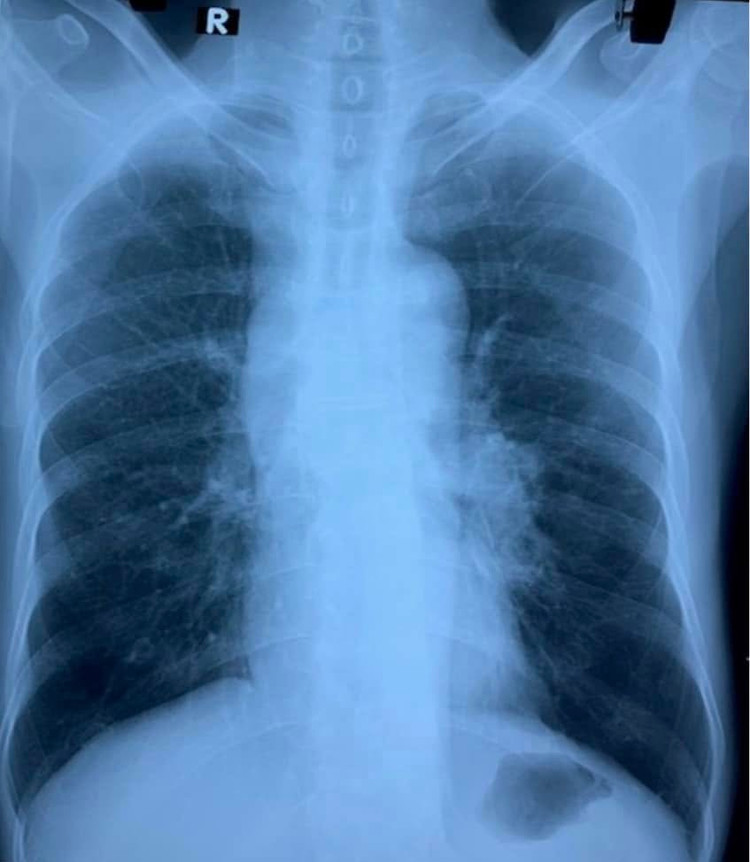

Qua thăm khám, bệnh nhân N. được bác sĩ chỉ định làm các xét nghiệm, siêu âm và chụp X quang. Kết quả phim X quang phổi thường cho thấy rốn phổi trái tăng đậm hơn so với bên phải.

| Ảnh chụp X-quang phổi người bệnh. Ảnh: BVCC. |

Bệnh nhân được chỉ định chụp cắt lớp vi tính lồng ngực. Hình ảnh cho thấy khối vùng trung thất và rốn phổi trái, bờ không đều, ngấm thuốc ở thành khối và vào các vách bên trong. Tổn thương hướng tới u phổi, dạng u phế quản trung tâm, xâm lấn trung thất, gây hẹp phế quản gốc trái.